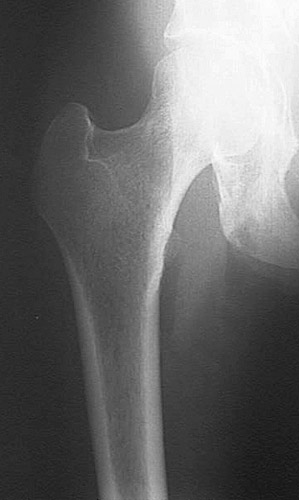

Seen here is the upper femur at the hip. There is severe osteoporosis with marked loss of bone density.